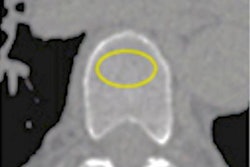

Prior research has demonstrated that a patient's CAC score is an effective predictor of future heart disease and that early detection of disease via CAC scoring could reduce the number of deaths. But having to read exams that turn out not to have CAC can slow the workflow in a busy radiology department. That's where deep learning can help, according to van den Oever and colleagues.

Van den Oever's group explored the feasibility of using a deep-learning algorithm to do just that. The team collected data from the ROBINSCA (Risk Or Benefit IN Screening for CArdiovascular diseases) study, a randomized CT screening trial, and the ImaLife (Imaging in Lifelines) study, which investigates imaging biomarkers for lung cancer, chronic obstructive pulmonary disease, and coronary artery disease.